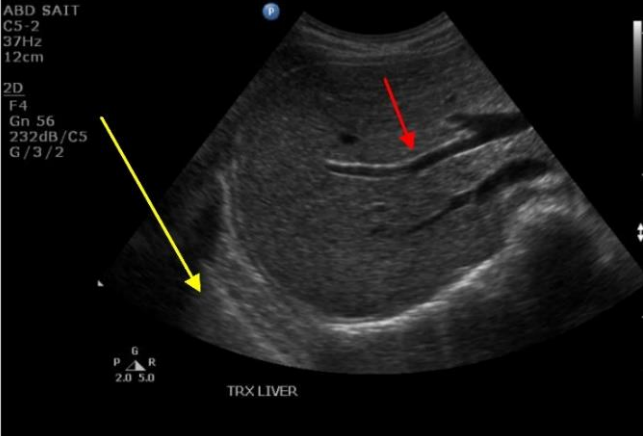

19

Q

What term best describes the echogenicity of the liver?

A

Hyperechoic to the kidney